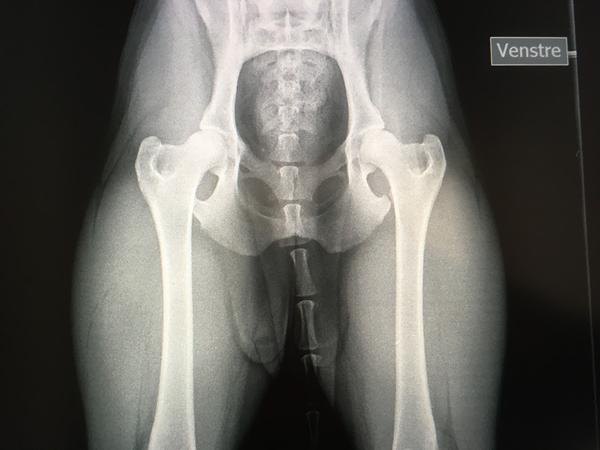

#1   7. jun 2017 Her er lige et billede mere smiley

• #3   7. jun 2017 Ligger hunden ikke helt forkert? Benene skal være i en anden position for at DKK godkender dem, tænker jeg.

• #4   7. jun 2017 Hvem Søren har taget de billeder?

Benene skal ligge lige ned og parallelt.

De billeder er helt forkert taget - og ud fra dem er hofterne ikke gode.

Men det er jo umuligt at vurdere, når billederne ikke er korrekte.

#9   7. jun 2017 Det er så beviset på at ikke enhver dyrlæge er i stand til at tage HD billeder.

Jeg er ret nysgerrig om det er dyrlægen der har bedømt billederne, eller om det er DKK, for jeg kan ikke i min vildeste fantasi forestille mig DKK godkende de billeder, med en hund der ikke ligger rigtigt.

#10   7. jun 2017 Hunden skal ligge på denne måde, og det trænede øje vil kunne se at det her er A hofter.

Bedømt hos DKK

• #12   7. jun 2017 Hvis det er det bedste hunden kan strækkes ud, så er der enten noget galt med dyrlægen eller hunden.

Hofterne ser også skidt ud smiley

• #14   7. jun 2017 Jeg er meget enig, hunden ligger helt forkert og skævt og sikke dog nogle mørke og uskarpe billeder?!

Og jeg er enig i at det ikke er pæne hofter, men om det er fordi billederne er dårlige, det ved jeg ikke.

Det er dyrlægen der har vurderet billederne og har vurderet til D hofter.

Og har også mærket på hende, og ud fra det vurderet D hofter.